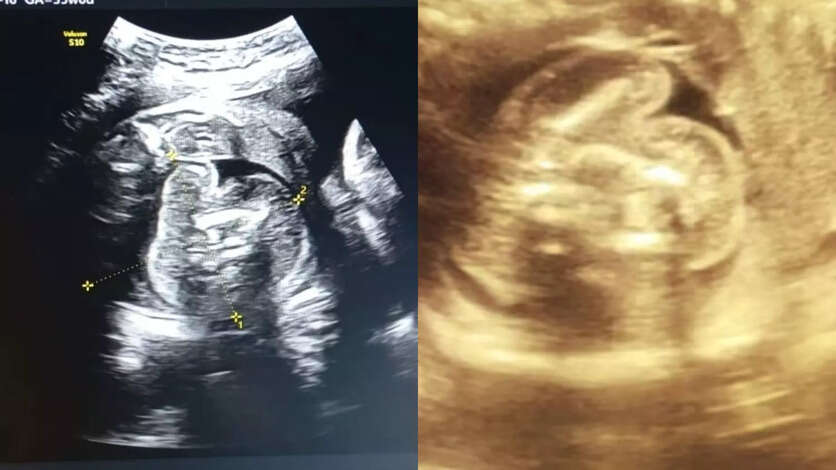

அரிதினும் அரிதான நிகழ்வு..! கர்ப்பிணிப் பெண் வயிற்றில் உள்ள குழந்தைக்குள் வளரும் கரு!

மகாராஷ்டிராவில் புல்தானா மாவட்டத்தின் அரசுப் பெண்கள் மருத்துவமனையில் 35 வார [9 மாத] கர்ப்பிணியான 32 வயது பெண் ஒருவருக்கு சோனோகிராபி செய்தபோது அவரின் ‘கருவில் கரு’ [Foetus inside foetus] வளருவது கண்டறியப்பட்டது.

அதாவது பெண்ணின் வயிற்றுக்குள் உண்டாகியுள்ள குழந்தையின் உடலினுள் மற்றொரு முழு வளர்ச்சியடையாத கரு உருவாகி உள்ளது.

இதுகுறித்து அந்த மருத்துவமனையின் மகப்பேறு மருத்துவர் பிரசாத் அகர்வால் கூறுகையில், ஆரம்பத்தில் நான் ஆச்சரியமடைந்தேன், பின்னர் கவனமாக ஸ்கேனை மறுபரிசீலனை செய்தேன்.

இது முந்தைய சோனோகிராஃபியில் தவறவிடப்பட்டது. ஏனெனில் இது மிகவும் அரிதான நிலை, இது போன்ற ஒரு நிலை இருக்கும் என்று யாரும் கற்பனை கூடச் செய்ய முடியாது. எனவே, நான் இரண்டு மருத்துவர்களிடம் விரிவான ஆலோசனைக்குப் பின் அதை உறுதி செய்தேன் என்று தெரிவித்தார்.

மேலும், குழந்தை பிறந்த பின்னரே இந்த நிலை பெரும்பாலும் கண்டறியப்படும். ஆனால் இப்பெண்ணுக்கு பிரசவத்துக்கு முன்னரே கண்டறியப்பட்டுள்ளது.

இது 5 லட்சத்தில் ஒருவருக்கு மட்டும் நிகழக்கூடிய அரிய வகையான மருத்துவ நிலை. இதுவரை உலகில் வெறும் 200 பேருக்கு மட்டுமே இந்த நிலை உண்டாகியது. அதில் இந்தியாவில் 15-20 பேரில் மட்டுமே இந்த நிலை பதிவாகியது என்று தெரிவித்தார்.

இந்த நிலைக்கான சரியான காரணம் முழுமையாகப் புரிந்து கொள்ளப்படவில்லை, ஆனால் இது ஒரே மாதிரியான இரட்டையர்களின் வளர்ச்சியின்போது நிகழும் ஒழுங்கின்மையின் விளைவு என நம்பப்படுகிறது.